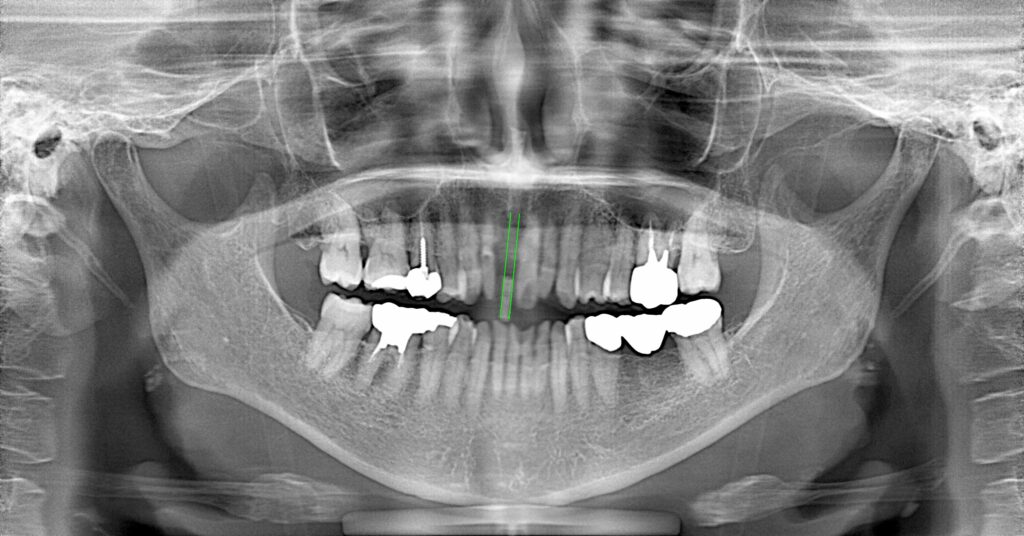

症例一覧 インプラント症例1 2024.11.25 治療内容インプラント主訴前歯部破折したためインプラント治療を行いたい費用¥671,000(1本)治療期間8ヶ月 インプラント症例2 前の記事 インビザライン症例2 次の記事